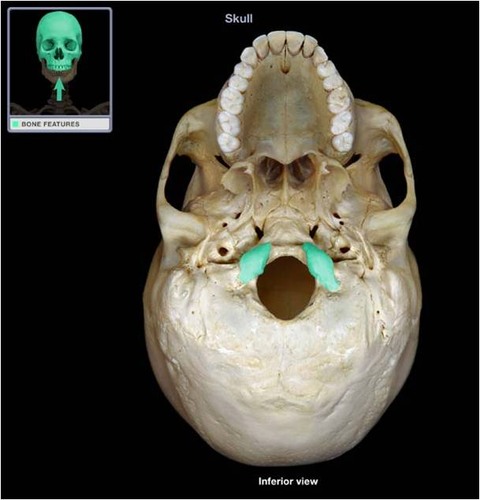

zygomatic bone (inferior)

sphenoid bone (inferior)

vomer (inferior)

mandibular fossa

mastoid projection

occipital condyle

foramen magnum

occipital bone

palatine bone